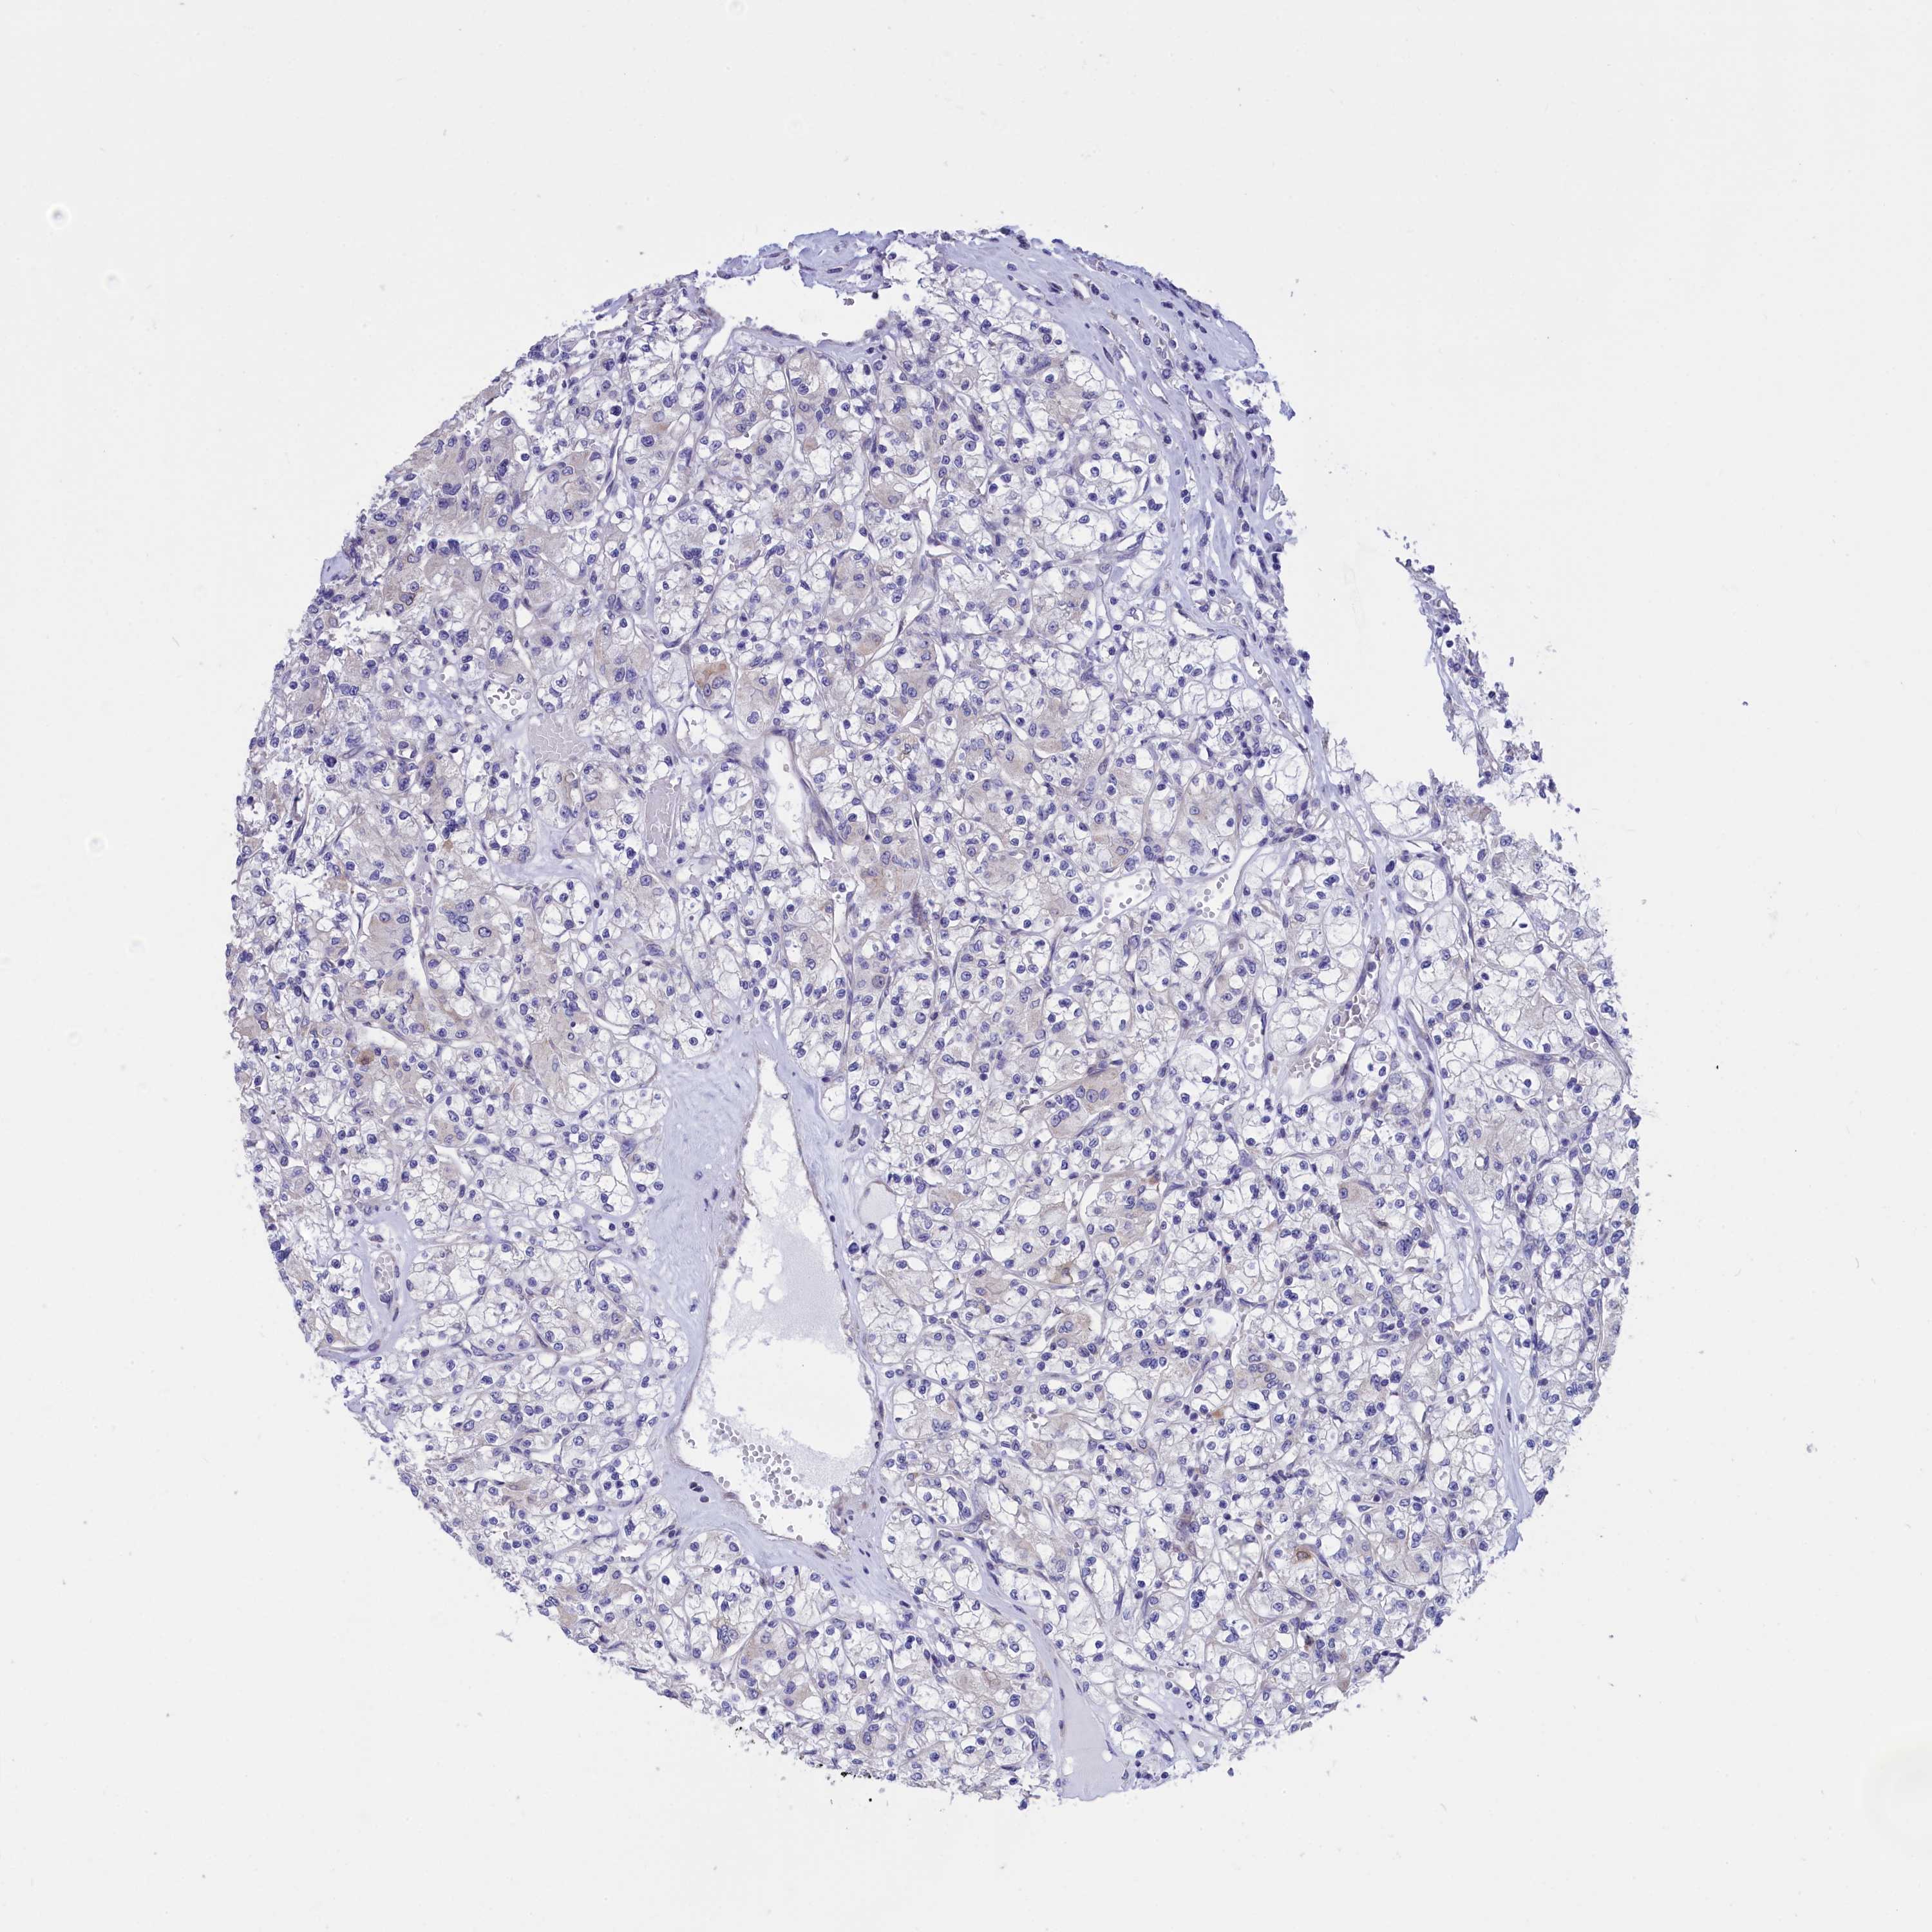

KIDNEY RENAL CLEAR CELL CARCINOMA (TCGA) - Interactive survival scatter ploti

The Survival Scatter plot shows the clinical status (i.e. dead or alive) for all individuals in the patient cohort, based on the same data that underlies the corresponding Kaplan-Meier plots. Patients that are alive at last time for follow-up are shown in blue and patients who have died during the study are shown in red.

The x-axis shows the expression levels (FPKM) of the investigated gene in the tumor tissue at the time of diagnosis. The y-axis shows the follow-up time after diagnosis (years). Both axes are complimented with kernel density curves demonstrating the data density over the axes. The top density plot shows the expression levels (FPKM) distribution among dead (red) and alive patients (blue). The right density plot shows the data density of the survived years of dead patients with high and low expression levels respectively, stratified using the cutoff indicated by the vertical dashed line through the Survival Scatter plot. This cutoff is automatically defined based on the FPKM cutoff that minimizes the p-score. The cutoff can be changed by dragging the vertical line or by entering a cutoff value in the square labeled "Current cut-off".

Under the Survival Scatter plot the p-score landscape (black curve; left axis) is shown together with dead median separation (red curve; right axis). Dead median separation is the difference in median mRNA expression between patients who have died with high and low expression, respectively. It is calculated as follows: median FPKM expression of dead patients with high expression - median FPKM expression of dead patients with low expression. This is intended to aid the user in visually exploring custom cutoffs and the associated p-scores and dead median separation.

Individual patient data is displayed and can be filtered by clicking on one or more of the category buttons on the top of the page. Categories describing expression level and patient information include: high, low, alive, dead, female, male and tumor stages. The scale of the x-axis can be toggled between linear and log-scale by clicking on the "x log" button. Mouse-over function shows TCGA ID, patient information and mRNA expression (FPKM) for each patient.

& Survival analysisi

Kaplan-Meier plots summarize results from analysis of correlation between mRNA expression level and patient survival. Patients were divided based on level of expression into one of the two groups "low" (under cut off) or "high" (over cut off). X-axis shows time for survival (years) and y-axis shows the probability of survival, where 1.0 corresponds to 100 percent.

CYP2U1 is potential prognostic, high expression is favorable in Kidney Renal Clear Cell Carcinoma (TCGA)

Best expression cut offi

Based on the FPKM value of each gene, patients were classified into two groups and association between prognosis (survival) and gene expression (FPKM) was examined. The best expression cut-off refers the FPKM value that yields maximal difference with regard to survival between the two groups at the lowest log-rank P-value. Best expression cut-off was selected based on survival analysis .

When clicking on this number, the vertical dashed line indicating cut-off, the interactive survival plot, and the Kaplan-Meier curve will be adjusted to show results based on the best expression cut-off.

: 3.42

P scorei

Log-rank P value for Kaplan-Meier plot showing results from analysis of correlation between mRNA expression level and patient survival.

N/A

TCGA RNA samplesi

RNA-seq data is reported as average FPKM (number Fragments Per Kilobase of exon per Million reads), generated by the The Cancer Genome Atlas (TCGA) .

Normal distribution across the dataset is visualized with box plots, shown as median and 25th and 75th percentiles. Points are displayed as outliers if they are above or below 1.5 times the interquartile range. FPKM values of the individual samples are presented next to the box plot.

Average pTPM 4.9

Number of samples 521